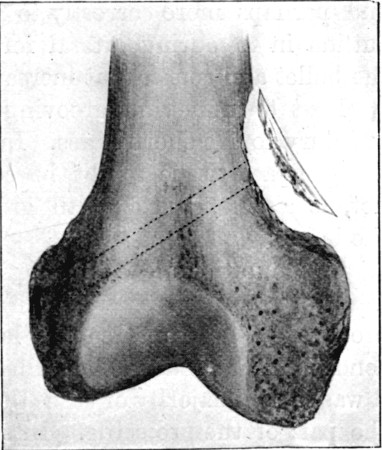

52. Oblique Perforation of Femur, Separation of Fragment at Exit Aperture in Bone169

62. Aperture of Entry into Frontal Bone 252